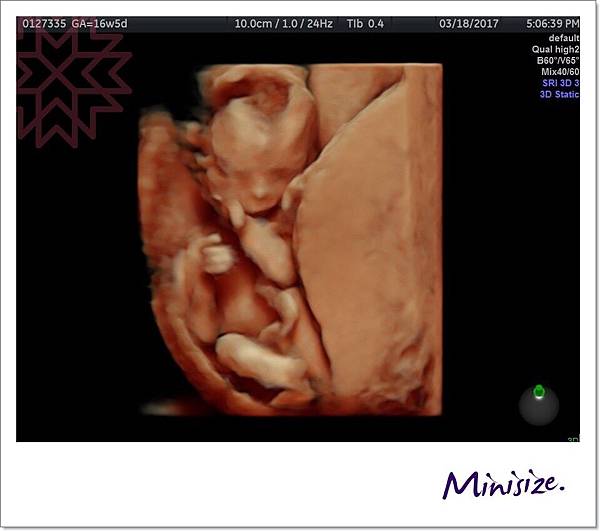

知道你們期待娃兒性別

寶寶也大方展現私密部位

一次讓爸爸媽媽看個精光不後悔

黃色圓圈處就是帶點亮光的小雞雞

寶寶:我是個小男生!!